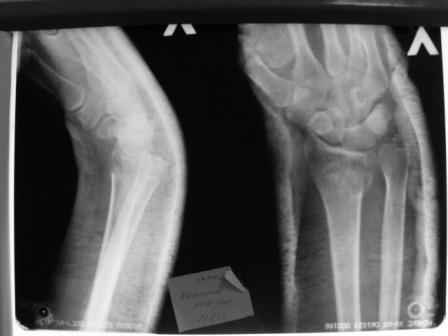

Уважаемые коллеги.Прошу обсудить случай лечения перелома дистального метаэпифиза лучевой кости. Ситуация скандальная и крайне неблагоприятная. Больная с патологической обстоятельностью мышления, склонностью к сутяжничеству, патологическими умозаключениями, не поддающимися коррекции (см. психиатрию, правда офиц. диагноза нет). В данном случае есть ряд ошибок с нашей стороны, прежде всего в отношении качества ведения документации (за что получил административное взыскание, по делом мне дураку). В остальном- придерживались в лечении подхода классический советской школы. Так как умную операцию…… сами знаете… 15.12- перелом луча в Москве. Там же репозиция, гипс. Дальнейшее лечение у нас в ЦРБ. 20.12.- вторичное смещение в гипсе21.12- под внутривенным наркозом- репозиция, гипсовая лонгета. Дальше начинается самое интересное. После репозиции больная заявила, что я (репозицию делал я) порвал ей все связки в суставе, посинел у нее 5 палец, якобы я за него тянул и т. д. На самом деле на 2 сутки после репозиции рука немного отекла и было незначительное сдавление гипсом, который был ослаблен. Дальнейшее лечение консервативное. Через 6 недель- гипс снят, назначено ЛФК. Пациентка крайне недовольна. Говорит, что на снимке у нее выступает кость, я ей сломал руку и.т.д. В общем началось. Пациентка прочитала в интернете наверное все, что есть по данной травме.По заключениями рентгенологов и консультанта из КДЦ областной больницы - стояние отломков допустимое. Объективно говоря- снижена высота лучевой кости, диастаз лучелоктевого сочленения, и не сросся шиловидный отросток. однако на РКТ при сравнении с другой стороной- разница незначительная. Дальше в одной из больниц нашей области и одной из больниц Москвы (вроде бы КГБ 53) врачи сказали, что репозиция сделана плохо. Нужна операция (восстановить длину лучевой кости), даже один из них предложил РЕДРЕССАЦИЮ (хи-хи) с наложением аппарата Илизарова. Что это для данной больной- радость неописанная. (см. описание психического статуса). Ничем другим, кроме зарабатывания дешевого авторитета объяснить данный факт не могу.Кстати, у больной еще нейропатия локтевого нерва.Для разрешения конфликта больная направлена на консультацию в ЦИТО на 03.03.11.

Теперь вопросы: 1.Прошу объективно оценить качество нашей репозиции на момент 21.12. (неужели так плохо?). Что на снимках при снятии гипса- сам вижу. 2. сравнить снимки РКТ (с двух сторон)- так ли велико укорочение лучевой кости и лучелоктевой диастаз. 3. Ваши мнения, в отношении целесообразности оперативного лечения учитывая ВСЕ вышеизложенное. 4. На всякий случай для суда- мог ли я тракцией в 2- 3 кг за 1 и 2 пальцы под внутривенным наркозом неправильно вколотить отломки и травмировать локтевой нерв. Кстати, в США если врач пациенту говорит, что его плохо лечили- то этого врача лишают лицензии. У нас наооборот- обгадить другого милое дело. И это процветает. От себя же могу сказать, что никто в нашем отделении так не поступает. Коллеги, будьте осторожны в своих высказываниях. От осложнений и ошибок никто не застрахован. А в данном случае многое будет зависеть от заключения консультантов поликлиники ЦИТО, куда больная направлена областным травматологом на 03.03 для решения вопроса о дальнейшей тактики лечения. С уважением ко всему травматологическому сообществу Дедок Михаил.

1. Репозиция от 21.12.10 была выполнена лучше, чем первичная.

2. Укорочение лучевой кости с изменениями дистального лучелоктевого сустава требует оперативного лечения